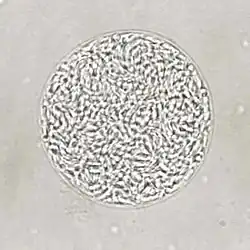

Dividing T. gondii parasites

T. gondii tissue cyst in a mouse brain. Individual bradyzoites can be seen within.